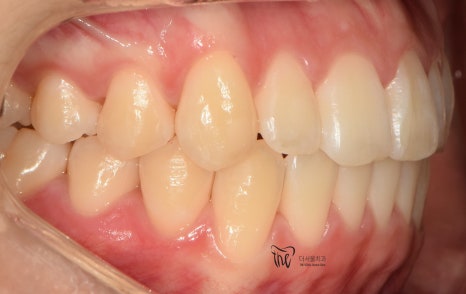

먼저, 임상 사진 5장을 보여드립니다.

그냥 겉으로 봤을 때는 단순 치아들의 불규칙성

때문에 치과에 내원을 하신 것으로 볼 수 있습니다.

그러나, 좌측에서 바라봤을 때는 어금니들이

부정교합을 띄고 있는 것을 볼 수 있습니다.

즉, 거꾸로 물리는 반대교합의 양상을 보여주고

있고 이런 증세 때문에 턱관절의 통증까지도

같이 느끼고 있는 채로 내원을 하셨습니다.

즉, ‘턱관절 통증 치료 및 치열의 개선’

이 2가지를 함께 치료를 받고 싶어서 먼 길을

걸어서 오셨던 환자의 임상 증례입니다.